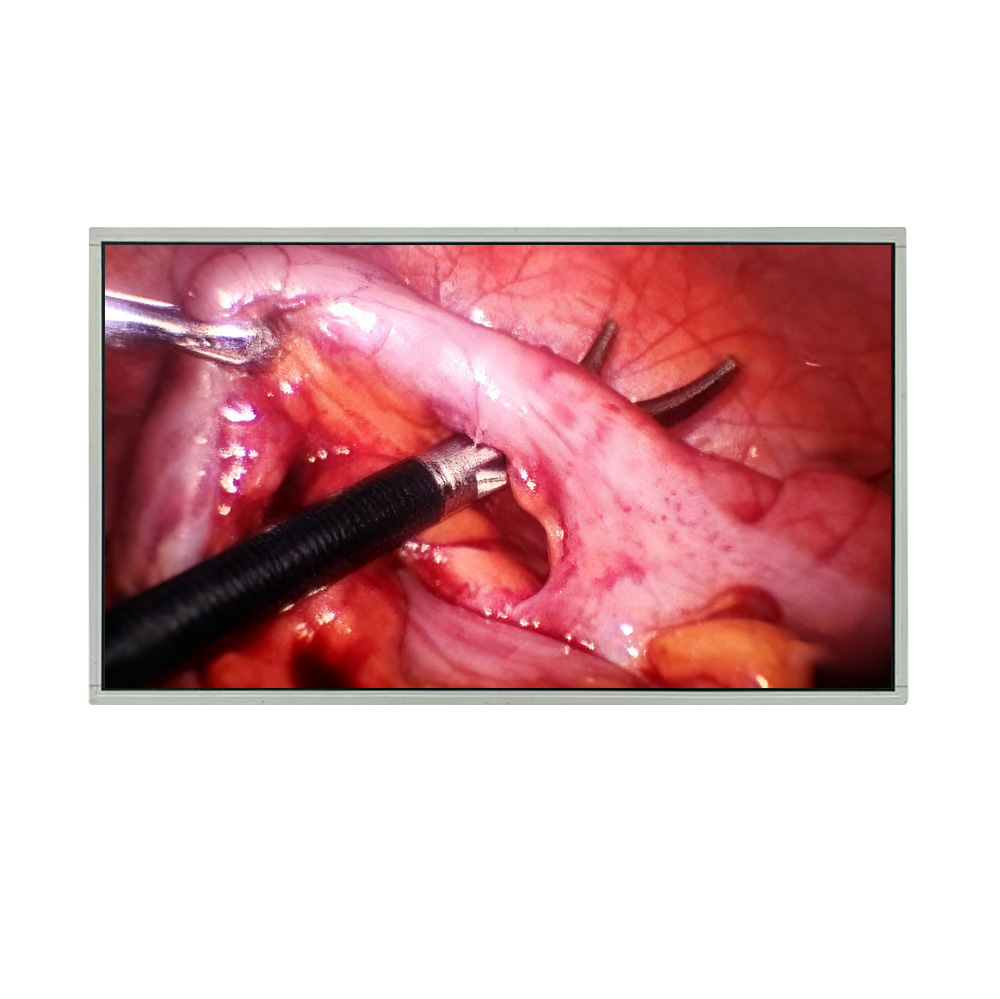

High Resolution Medical Display